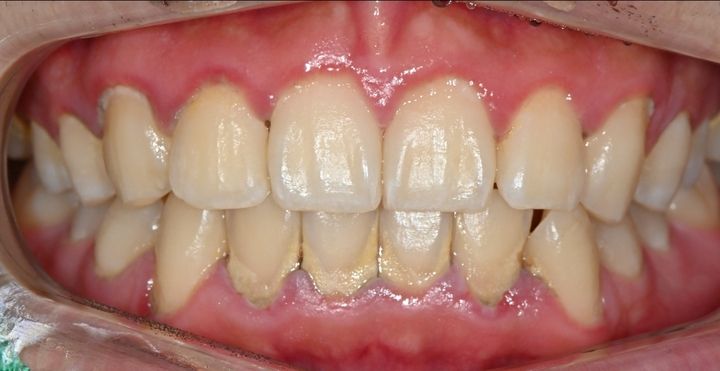

ハル歯科医院は、最先端のインプラント歯科治療に特化したクリニックです。代表のジョー・ハング院長は日本の神奈川歯科大学を卒業し、両国での歯科医師免許を保持。さらに、韓国で専門医資格を取得し、口腔外科など高度な手術経験も豊富です。すべての治療を院長自らが行う専任診療制を採用しており、流暢な日本語で対応可能。「デジタルインプラント」や「無削除ラミネート」などの最新のデジタル歯科治療を、日本の約半額で受けられます。仁川・金浦空港から乗り換えなしで行ける孔徳(コンドッ)駅すぐとアクセスも良好で、旅行者にも便利な立地となっています。

近所に住んでいる日本人でホワイトニングで訪れました。先生は日本語が流暢で歯科衛生士さんも少し日本語で対応していただけた為、安心感があります。一回のホワイトニングで歯が綺麗になったのでとても嬉しかったです。

今回ホワイトニングを1回受けました!

歯の色もすぐ白くなったし、凍みることもなかったです!